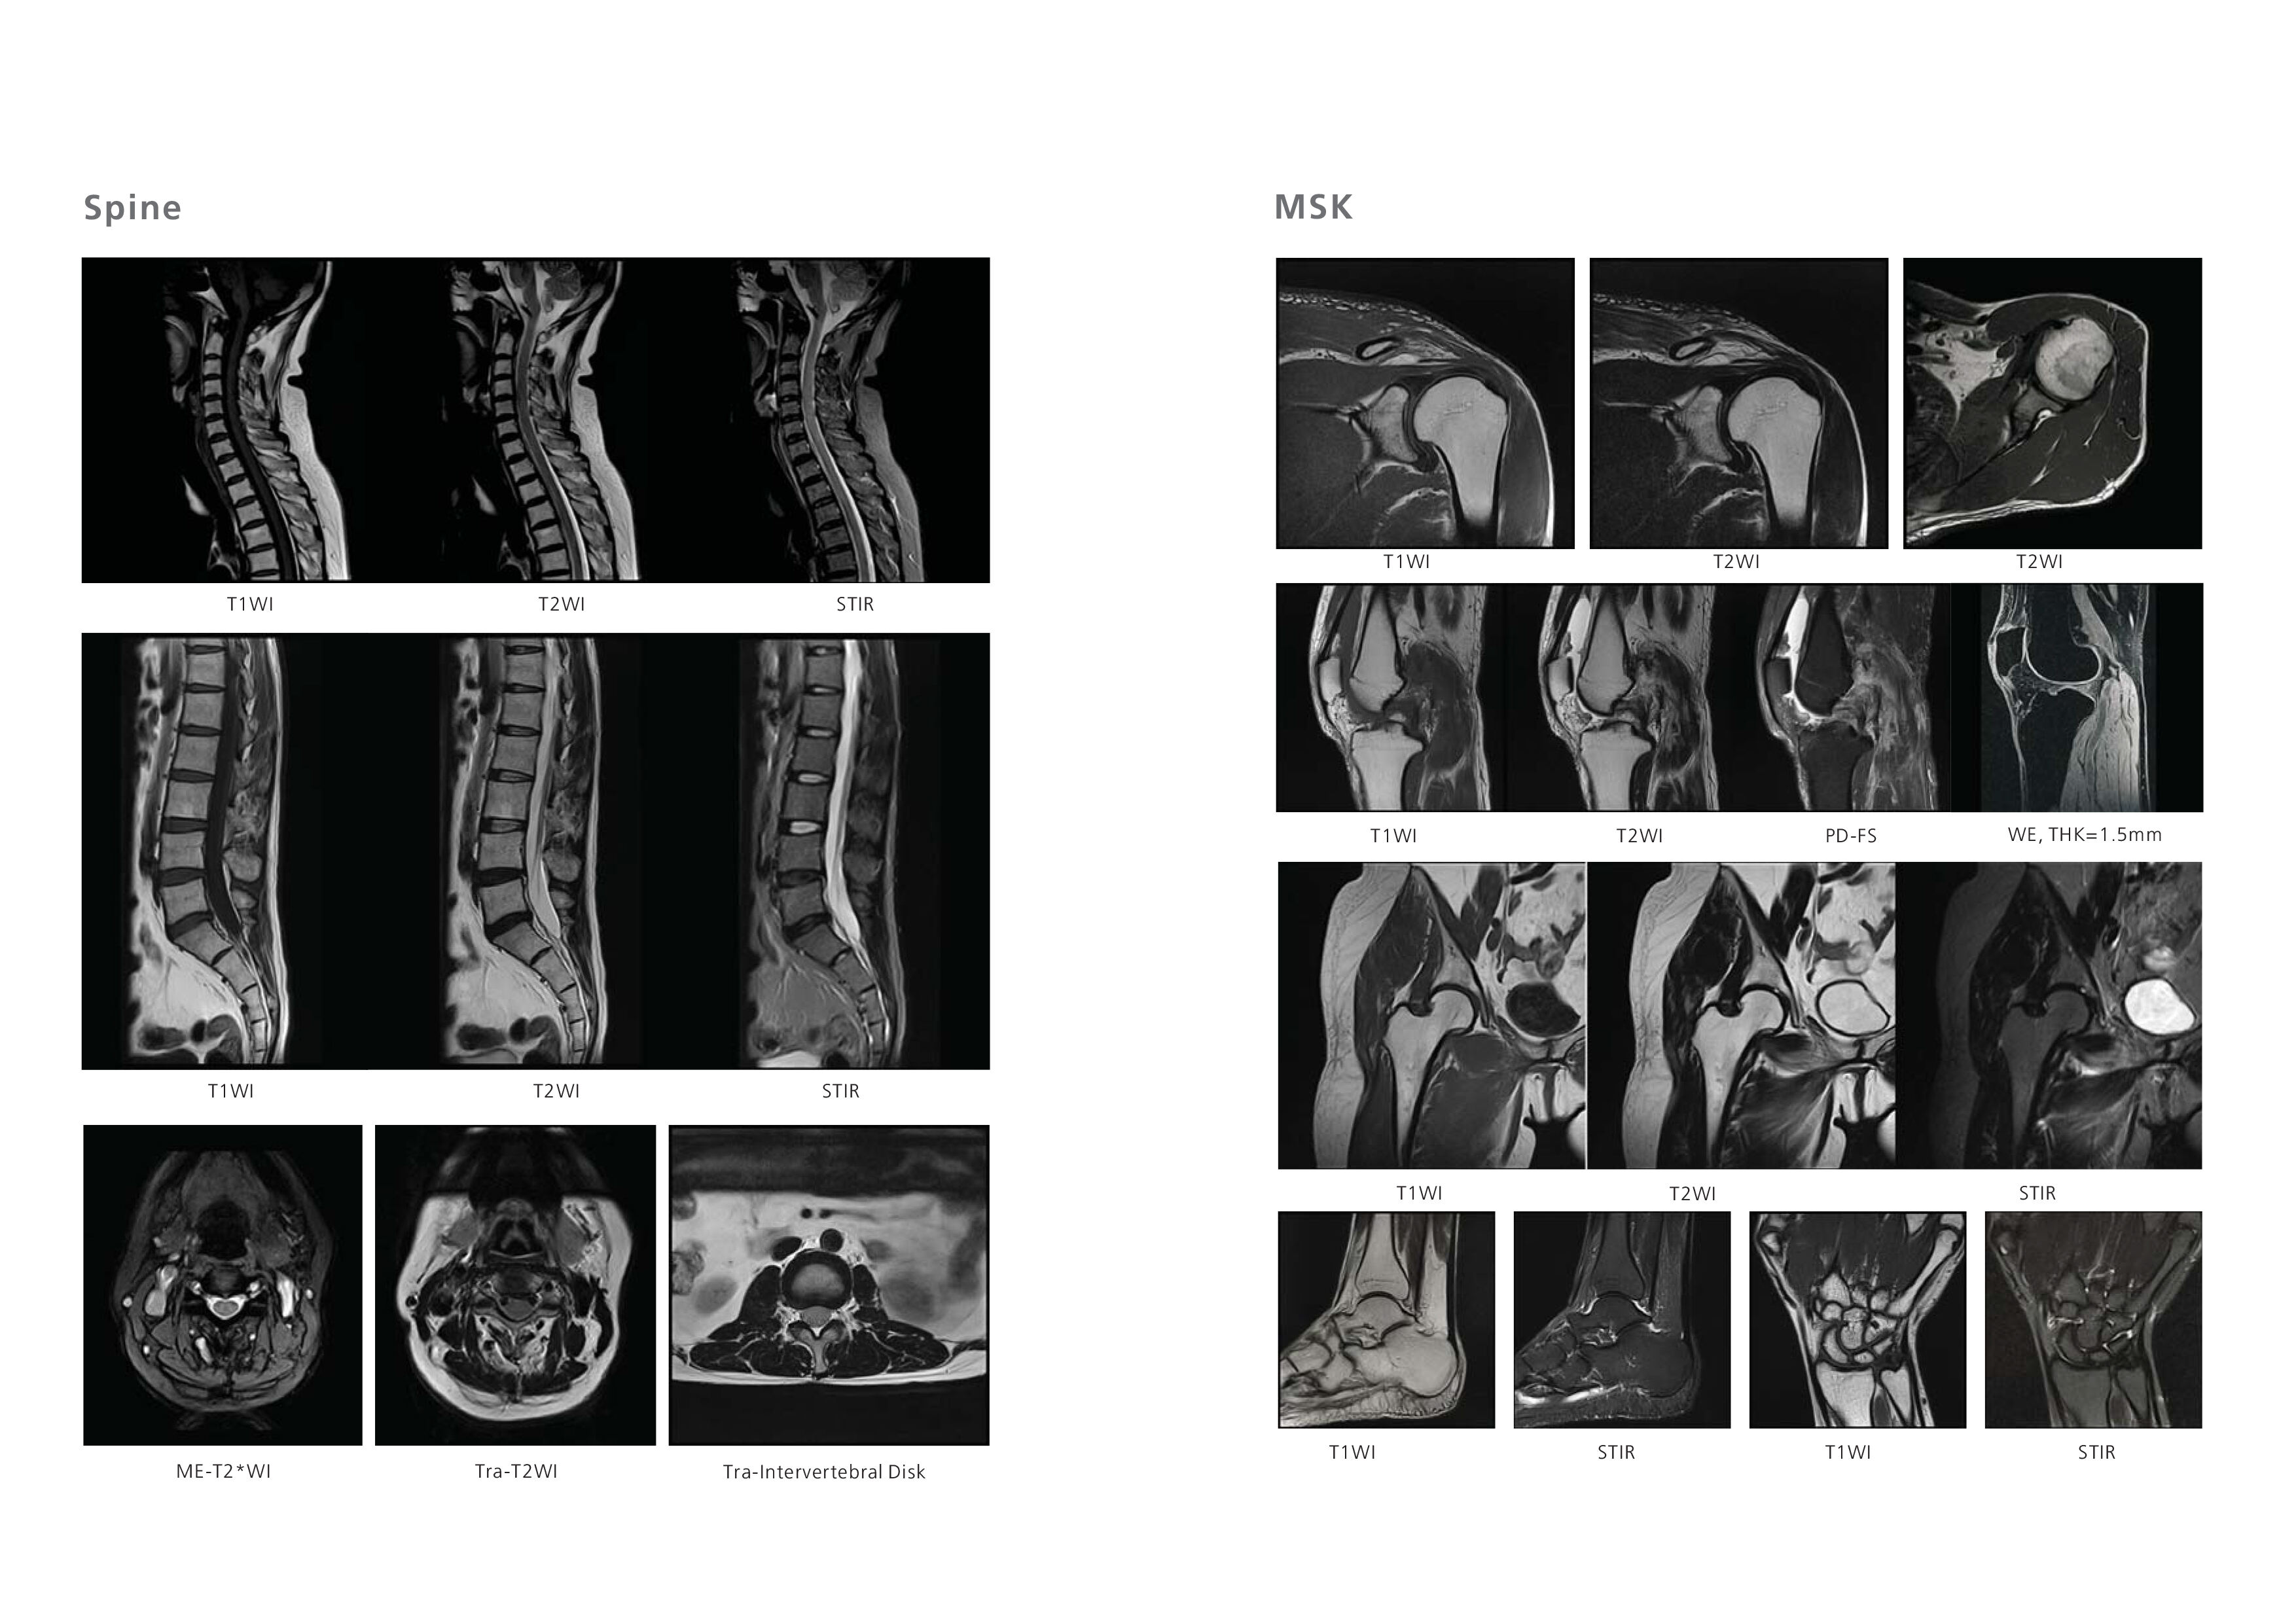

SuperMark 1.5T is a latest generation superconducting MRl system based on over 30 years of experience in research and development, which focuses on user's concerns. This system is equipped with a new upgraded hardware and software platforms with A-combi and Al technologies that benefit users a lot and deliver patients with more comfortable experiences. It features new user-friendly design, faster imaging speed, higher image quality and greatly improved work efficiency.

SuperMark 1.5T provides not only conventional pulse sequences and basic clinical applications, but also advanced functional applications. Moreover, it adopts brand new professional APEX operation system which ensures easy operation and fast diagnosis